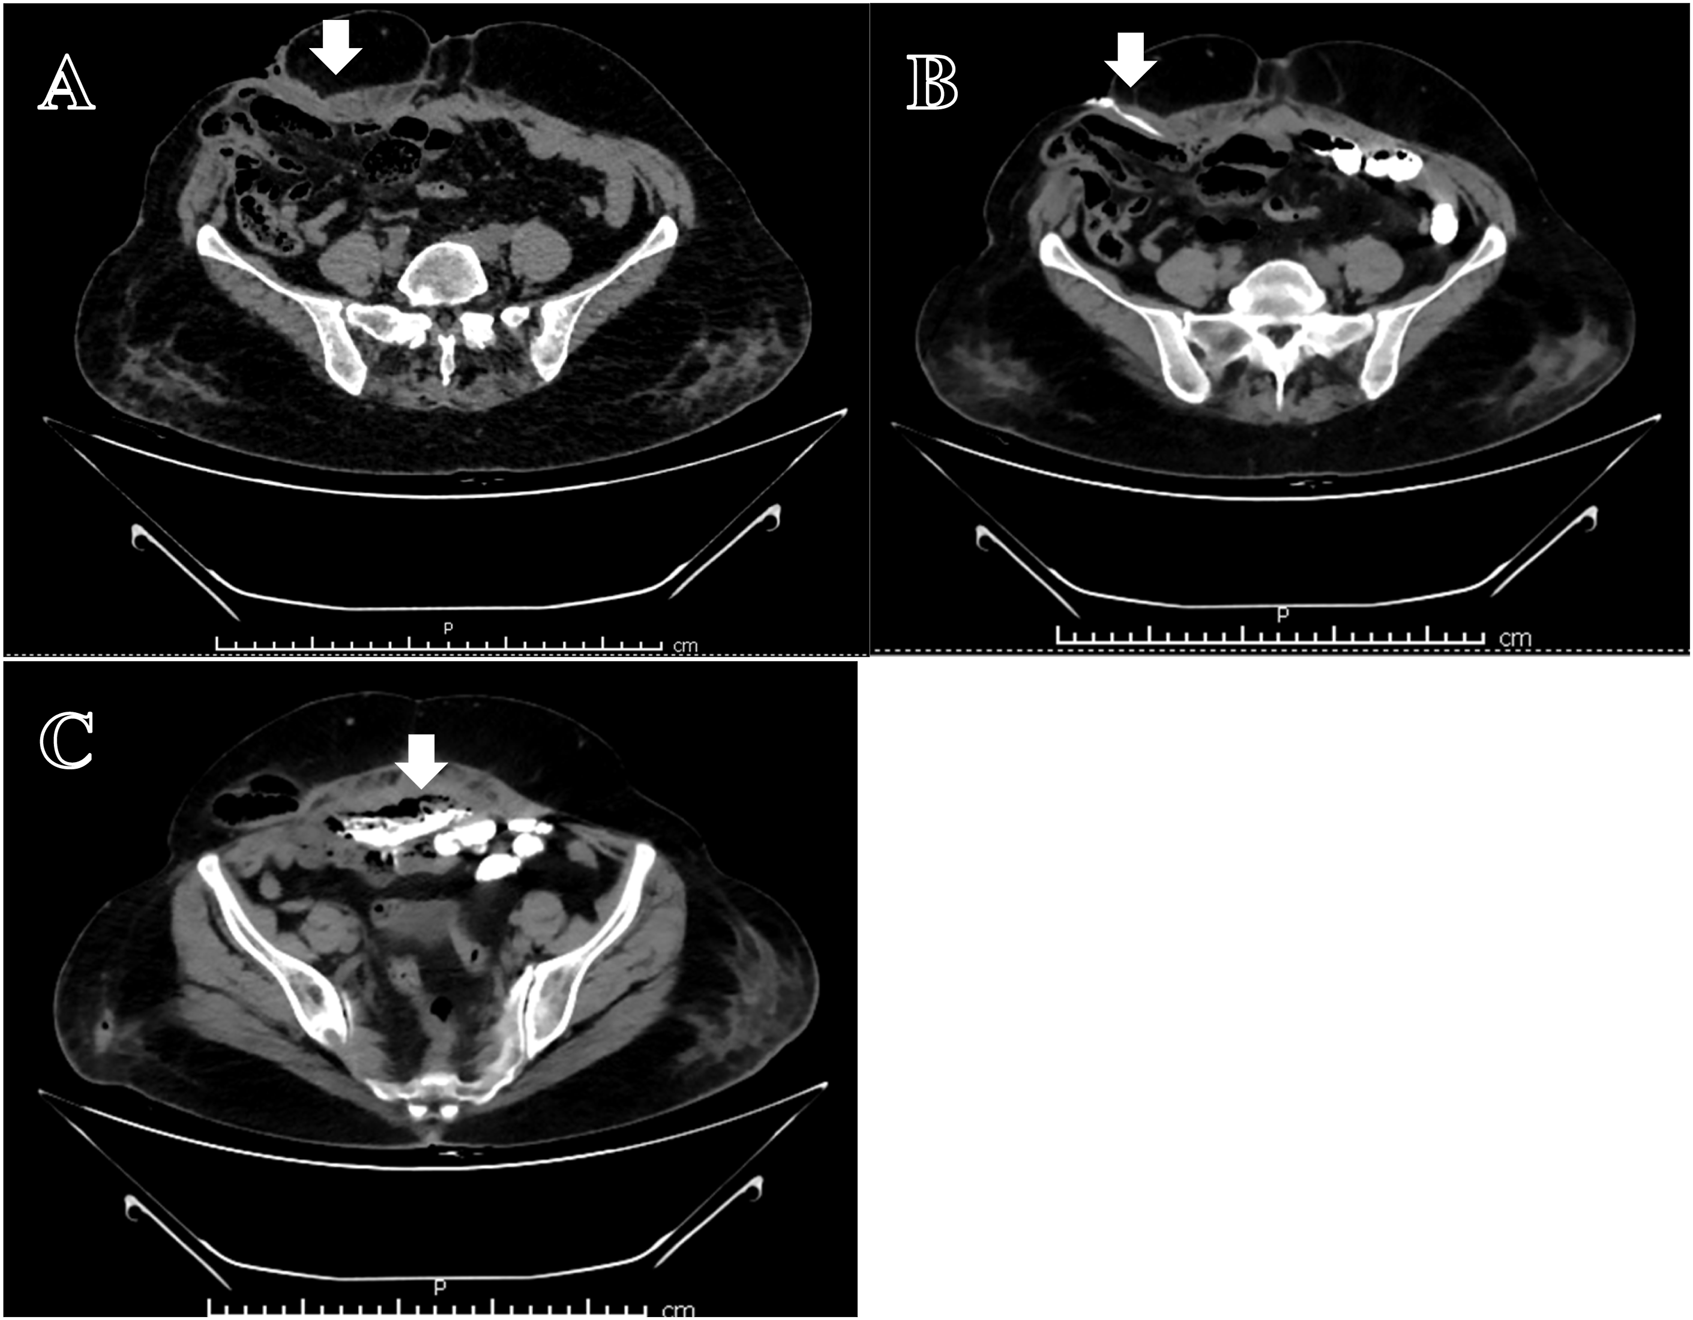

Evaluation: A CT fistulogram showed communication between the anterior abdominal wall, mesh, and distal jejunal loops [Figure 1].

CT Fistulogram: (A) Collection below anterior abdominal wall with external communication (arrow). (B) Contrast fistulogram-showing fistula in right lateral abdominal wall (arrow). (C) Contrast filling in the air containing collection with communication with the bowel (arrow).

The occurrence of fistula formation can take a few months to several years with rates ranging from <1% in clean surgeries (<1–2%) up to 20% (severe contamination/infection) with rates mentioned in different literatures ranging 1%–6% [7]. The cases presented show a diverse array of clinical manifestations of mesh erosion, from abdominal pain, bowel obstruction, and fistula formation to more severe symptoms like chronic discharge and sepsis. The mesh can even migrate transmurally from abdominal wall into bowel [8] [Figure 1]. Primary mesh migration occurs due to inadequate fixation or external forces, with displacement risks heightened by early post-operative activities [9]. Fixation can reduce displacement but increases adhesion and nerve injury risks. Secondary migration results from foreign body reactions causing mesh erosion through tissue planes. Sharp mesh edges can weaken walls and erode viscera, triggering inflammatory responses [10]. Clinicians should consider mesh erosion or migration in patients presenting with unexplained regional pain or bowel/urinary symptoms following prior hernia repair.

Mesh erosion and fistulisation often present with gas-filled fluid collections confirmed on imaging by oral contrast material extending outside the bowel lumen into fluid collections or abdominal wall tissues [11]. These cases underscore the diagnostic complexity of mesh erosion and fistula formation, which may not be fully appreciated through imaging alone.

CT imaging and fistulograms were crucial in identifying fistulous tracts and bowel involvement [Figure 1], but the extent of erosion was often only fully appreciated during exploratory surgery. For example, in Case 4, imaging revealed a large abdominal defect and adhered bowel loops, but the intraoperative findings of multiple small bowel fistulae and the inability to completely remove the mesh underscore the limitations of preoperative imaging in fully assessing the complexity of the situation. As seen in Case 6, the mesh erosion and incorporation into bowel wall may lead to diagnostic dilemma of malignancy which needs to be ruled out with biopsy and may require extensive surgical procedures. Similarly, in Case 7, colonoscopy and imaging showed only a small rectal polyp and pelvic collection, but surgery revealed a concealed caecal fistula and infected bilateral pubic mesh, confirming the underdiagnosed nature of low-grade erosive mesh complications.